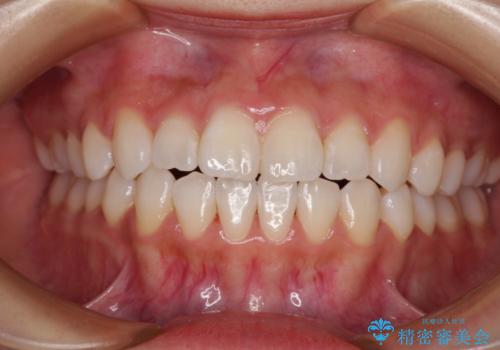

むし歯と前歯のデコボコを治したい インビザラインを使用した総合歯科治療

- 目立つ銀歯やむし歯、前歯のデコボコを気にして来院された患者様です。

しっかりと装着時間を守ってくださり、来院のタイミングに合わせてインビザラインの装着期間を調整するなど、協力いただいたおかけで、1年半の期間で全てを終えることができました。